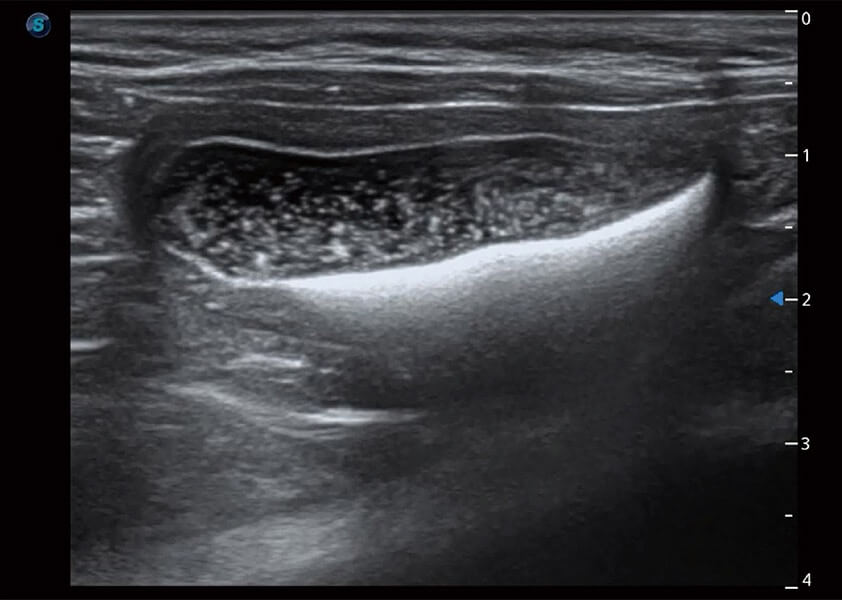

优异的基础图像

(犬)胆囊泥沙

(猫)膀胱结晶